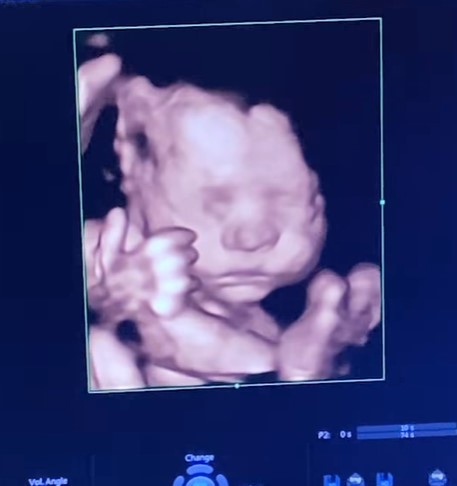

A while ago, Neeti Mohan's adorable sister, Mukti took to her IG handle and dropped a cutesy video on her nephew's birthday. The video featured several snippets from Aryaveer's childhood days. As the video began, we can see a sonography picture of Aryaveer. As the video proceeded, it showed when Aryaveer was born and taken to home. The video also showed Aryaveer spending quality time with his aunties, papa, mommy, and other family members. Through the video, we can witness how Aryaveer grew up while giggling, creeping and playing around the house with his little footsteps.